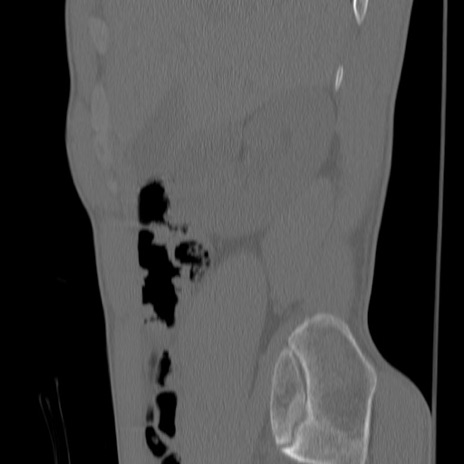

症例3 腰椎CT(矢状断像)

腰椎CT

冠状断像